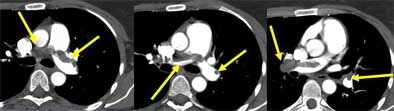

![]() |

| Vascular cutoff sign. Image courtesy of Dr. John Mayo. |

Moreover, a suspected saddle embolus doesn't justify a pulmonary angiogram, though surgeons and internists often seem to think it does, Mayo said. For one thing, a pulmonary angiogram is difficult to do in the presence of a large saddle embolus because it results in a dilated right ventricle. For another, saddle emboli create a significant flow blockage that is easily detectable on CT, he said.

| Saddle embolus. Images courtesy of Dr. John Mayo. |